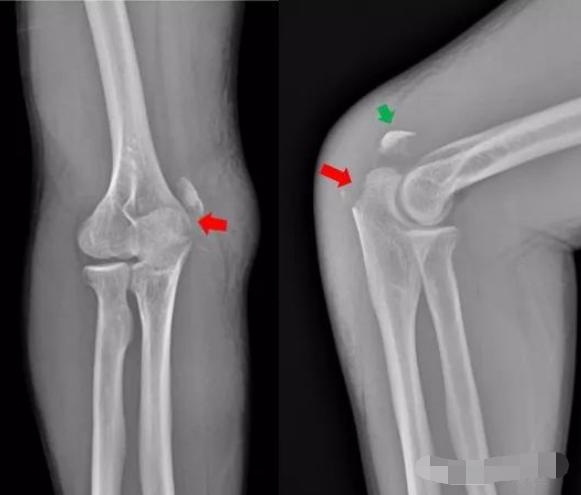

2、患者摔倒,右肘关节着地,拍片如下:

右肘关节内侧见游离骨碎片影,侧位示骨碎片位于右肘关节背侧,右尺骨近端背侧骨质部分缺如,右尺骨近端背侧撕脱性骨折。